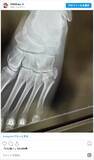

2025年9月1日、ロックバンド『ONEOKROCK』のボーカル、Takaさんが、Instagramを更新。メッセージ動画とレントゲン写真を投稿し、ライブ中に左足を骨折したことを報告しました。Taka...